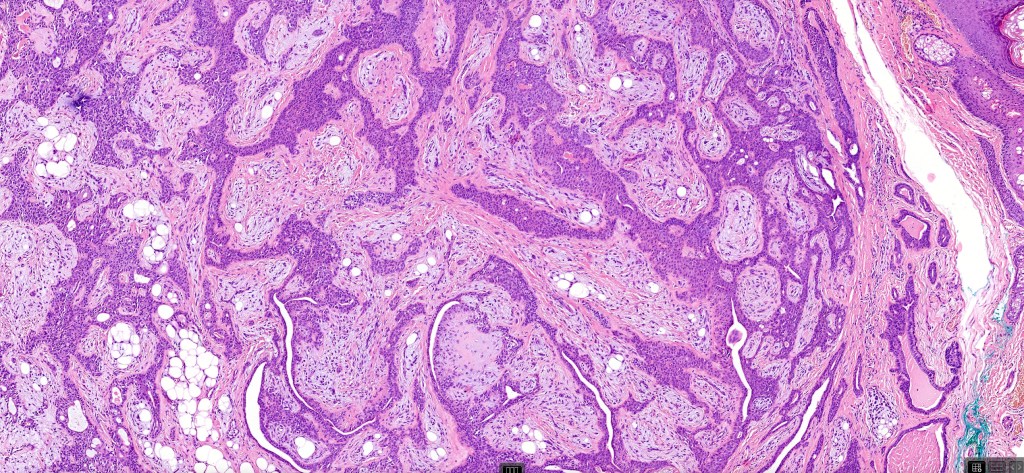

•Well circumscribed unencapsulated, nodular/multinodular silhouette composed of an admixture of epithelial & mesenchymal elements

•Often intensely basophilic due to mucinous deposits

•Mixed epithelial component including nests & cords of epithelium with abundant, eosinophilic cytoplasm & small vesicular nuclei

•Glandular differentiation sometimes showing apocrine differentiation

•Myoepithelial layer in glandular foci

•Ductal differentiation

•Follicular & sebaceous differentiation

•Keratocysts & squamous foci

•Stromal sclerosis & hyalinization

•Myxoid change

•Chondroid foci